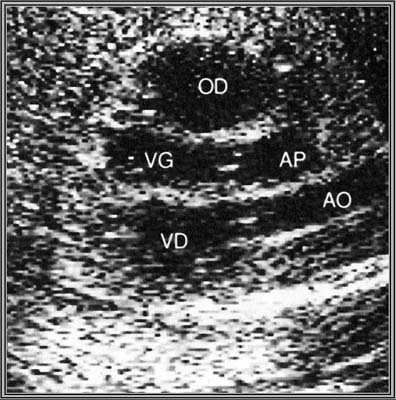

Echographiquement :

- Parallélisme des gros vaisseaux au niveau de valves semi-lunaires en incidence des cinq cavités ,

- Aorte antérieure naissant du VD

- AP postérieure naissant du VG et se divisant précocement

- En incidence transversale par les gros vaisseaux, visualisation simultanée des deux gros vaisseaux

- CIV dans 20 % des cas.